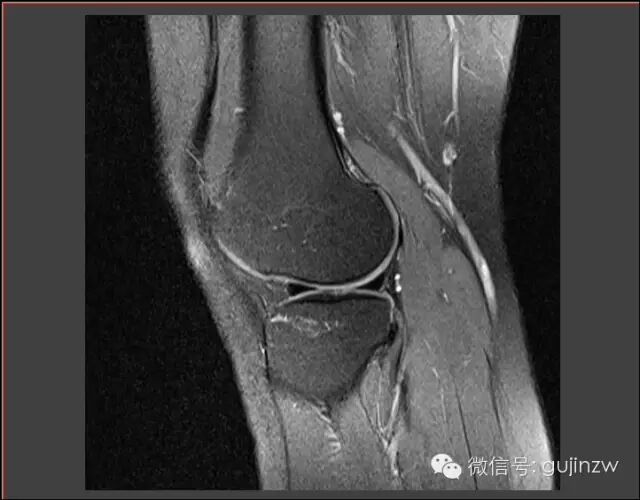

MRI常见征象

• 直接诊断半月板损伤:3度损伤,半月板形态异常,半月板与关节囊分离。

• 征象:蝴蝶结缺失征,多蝴蝶结征,双后叉征。

3度损伤

半月板形体异常、与关节囊分离

蝴蝶结缺失

双后叉征

多蝴蝶结征

MRI

关节镜